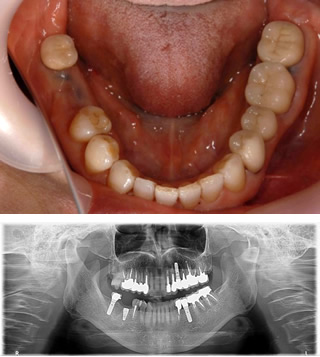

インプラント治療例2

• 1)平成26年11月21日 初診 64歳女性

右下の歯(矢印の歯)他院で抜いたほうがいいと言われ相談に来院。過去に3本他院にてインプラント経験あり。当医院でCT撮影をしたところはっきり歯牙に破折が起きており抜歯が必要と判断しました。

• 2)患者様もCT画像を見て納得されて当院でのインプラントを希望されました。抜歯後、歯肉が治るのを待ってインプラントを埋入しました。

• 3)平成27年6月2日 右下 旧インプラントと連結して上部構造をセットました。